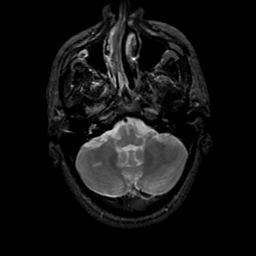

MR Study #22, December 1, 1991 -- Slice #10

[Home][Help][Clinical][Tour 1][Tour 2] Slice 10